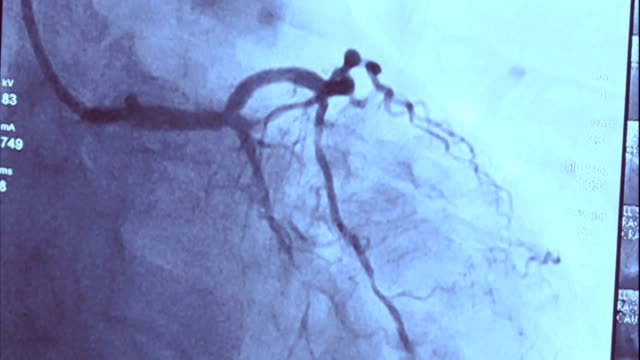

관상동맥 석회화를 검사하기 위해 CT 검사를 사용합니다. 이 검사로 석회화된 혈관 내 벽의 정도와 범위를 확인할 수 있으며, 석회화 양을 수치로 계산할 수 있습니다. 일반적으로 석회화 수치는 0점부터 시작하며, 수치가 높을수록 중증의 석회화를 의미합니다.

추가 검사는 심근 허열 여부를 확인하는데 도움을 줍니다. 이를 위해 운동 부하 검사, 태그약 스펙트 검사 등이 시행될 수 있으며, 속해할지 여부를 판단하기 위한 관상동맥 조영술도 필요한 경우에 시행됩니다.